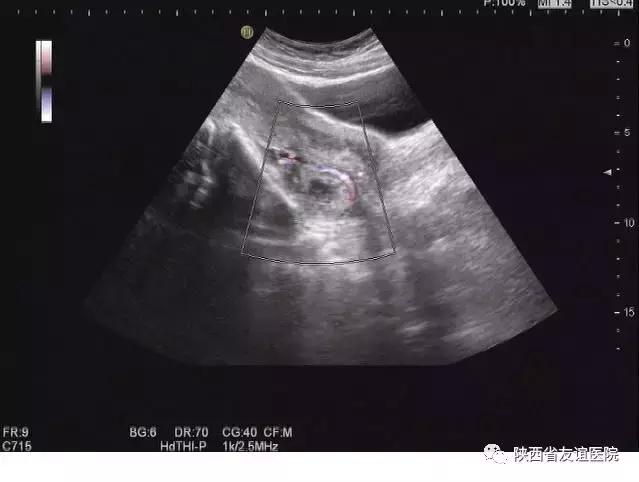

宫外孕B超图

三是产检能查出胎儿所有的畸形

B超作为产科中最常用的影像学检查手段,同样也被准爸妈们“寄予厚望”,认为B超能够检查出所有的胎儿畸形。

其实,胎儿的畸形有成千上万种,主要包括染色体畸形和形态畸形,根据超声检查的原理,只有形态上表现出来的畸形才能被超声所检查出来,当然这其中也包括染色体畸形中伴随形态畸形的胎儿。而那些染色体异常,形态上却没有异常表现的胎儿,B超是“无能为力”的,必须借助其他产科检查手段才能筛查出来。

所以,B超虽然是常用且实用的检查手段,但B超却不是“无所不能”的,任何一种检查手段都是有局限性的。因此,建议孕妈妈们遵照产科医生的建议,结合其他检查手段,按时进行各项产前检查,尽早排除畸形。